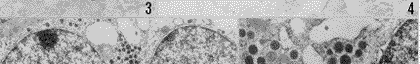

图1~4 免疫组织化学PAP法,Ehrlich苏木精复染

图2~3 溃疡后10d、14d大鼠胰岛,A细胞明显增多 ×400

图4 溃疡后14d大鼠胰腺小叶间、小导管周围散在的胰高血糖素免疫反应性细胞及小胰岛 ×200

Fig.1 The rat islet A cells in NCG. ×400

Fig.2-3 The number of A cells increased remarkedbly on 10 and 14 days in EUG. ×400

Fig.4 The sparse Glu-IR cells and small islets among pancreatic lobules and around small ductus on the 14th day in EUG. ×200